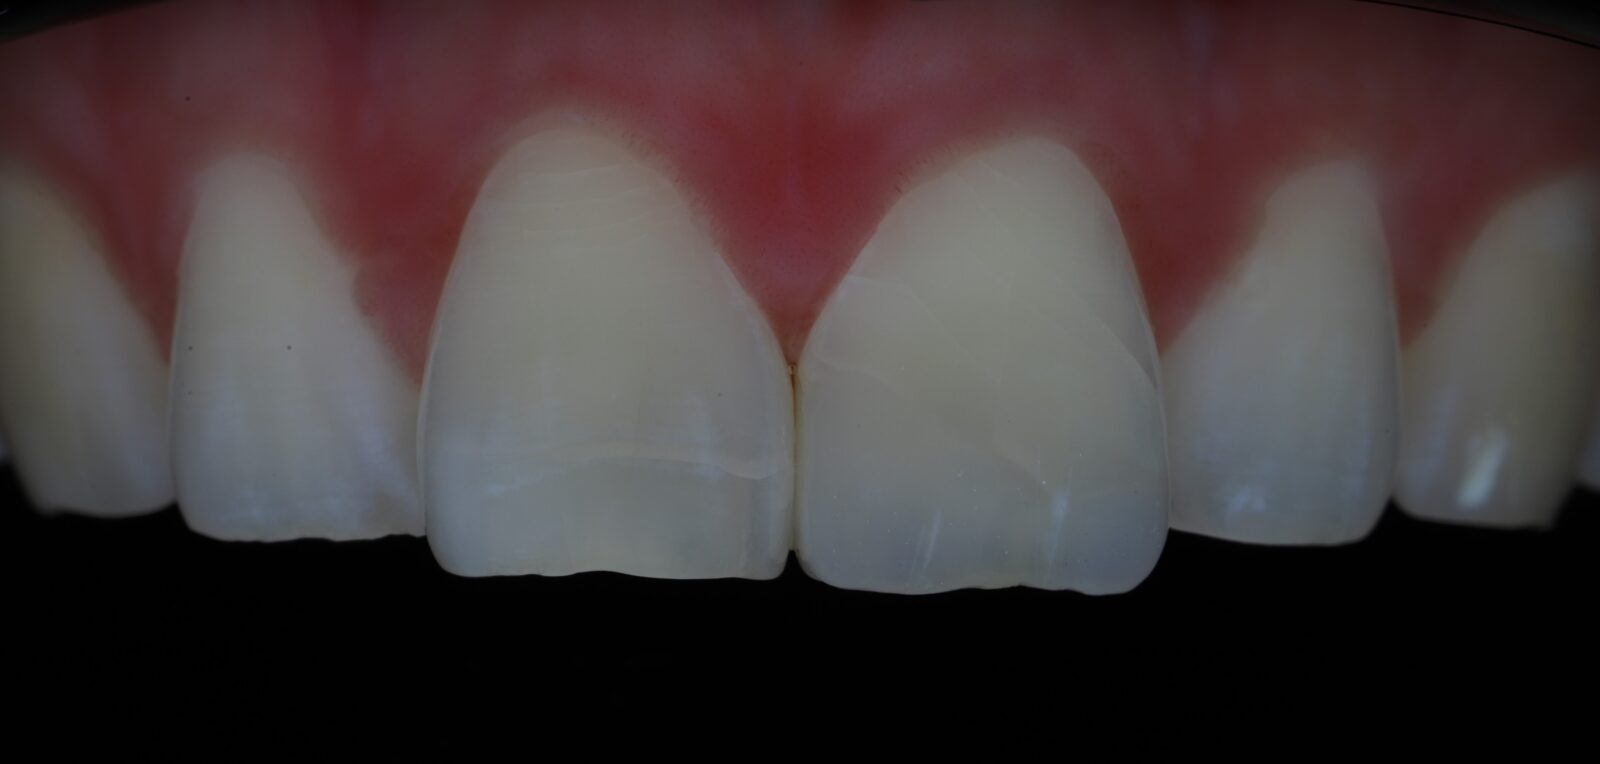

Спустя 6 месяцев после травмы окончательно отреставрировали 2.1 зуб. (фото после снятия коффердама, пациент больше не явился на осмотр)

Спустя 6 месяцев после травмы. (белая полоска около десны вследствие лечения в коффердаме)

Наблюдение: Фотографии спустя 1 год и 8 месяцев. 22.06.2024г.

Была проведена незначительная корректировка и отполировали до блеска

Фотография с поляризационным фильтром